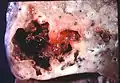

Image de pathologie d'un abcès pulmonaire.

Un abcès sous-pleural.